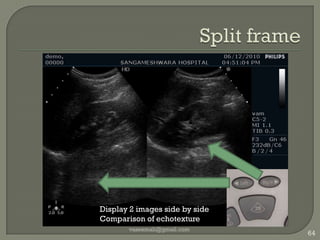

Split framevaseemali@gmail.com64Display 2 images side by sideComparison of echotexture